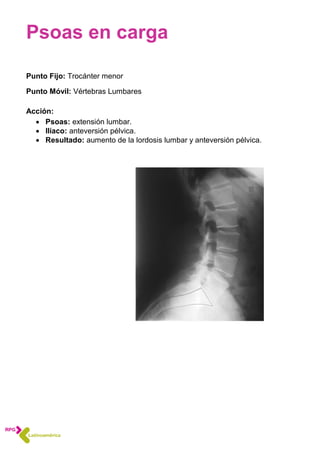

Psoas en carga

Punto Fijo: Trocánter menor

Punto Móvil: Vértebras Lumbares

Acción:

 Psoas: extensión lumbar.

 Ilíaco: anteversión pélvica.

 Resultado: aumento de la lordosis lumbar y anteversión pélvica.